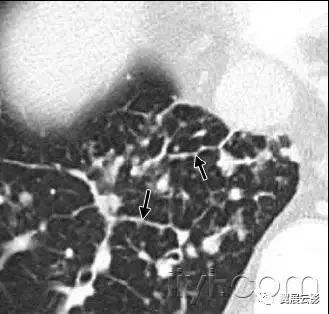

十八、小叶中心性:

解剖:小叶中心性用于描述次级肺小叶的支气管血管束中心区域。病理学上也用这一术语描述终末小支气管远端,位于呼吸性细支气管和肺泡管中心的病变。

CT:正常次级肺小叶中心的点状或者线状的密度增高影,胸膜下25px范围内最明显,代表小叶内的动脉,直径约1mm。

小叶中心性异常包括(1)结节(2)树芽征,提示小气道病变(3)由于临近间质的增厚或者浸润导致小叶中心结果更加清晰(4)小叶中心性肺气肿导致的异常低密度。

附图为小叶中心性肺气肿